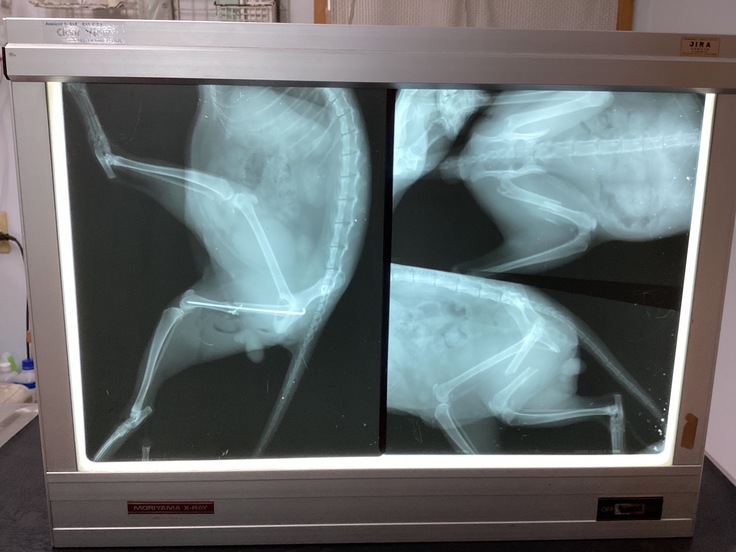

⚫︎サンちゃん♂ 人馴れした地域猫。何があったか不明ですが、右後ろ足を骨折していました。発見時、骨折から1週間程経っていて、難しい手術になったようですが、無事に手術してもらうことができました。大きなエリザベスカラーと脚の保護具を付けてもらい、10日間入院して順調に回復しています。